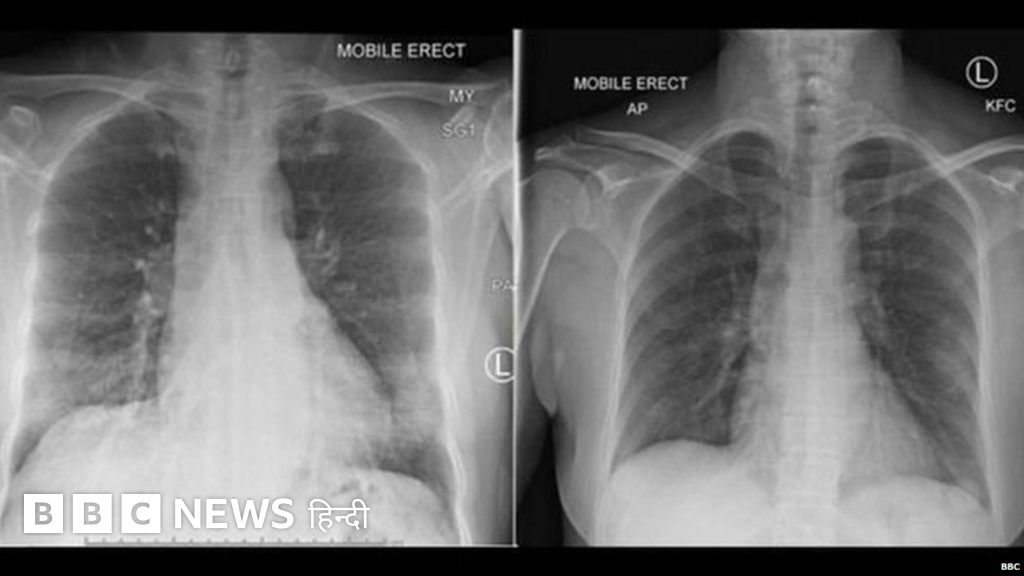

इन कोशिकाओं का पता एक संक्रमित महिला की जांच से किया गया. उन्हें मामूली-मध्यम संक्रमण था और उसे इसके अलावा दूसरी कोई भी बीमारी नहीं थी.

चीन के वुहान शहर की एक महिला को संक्रमण के बाद ऑस्ट्रेलिया के एक अस्पताल में भर्ती कराया गया था. भर्ती कराये जाने के 14 दिनों के भीतर वो पूरी तरह स्वस्थ हो गईं.